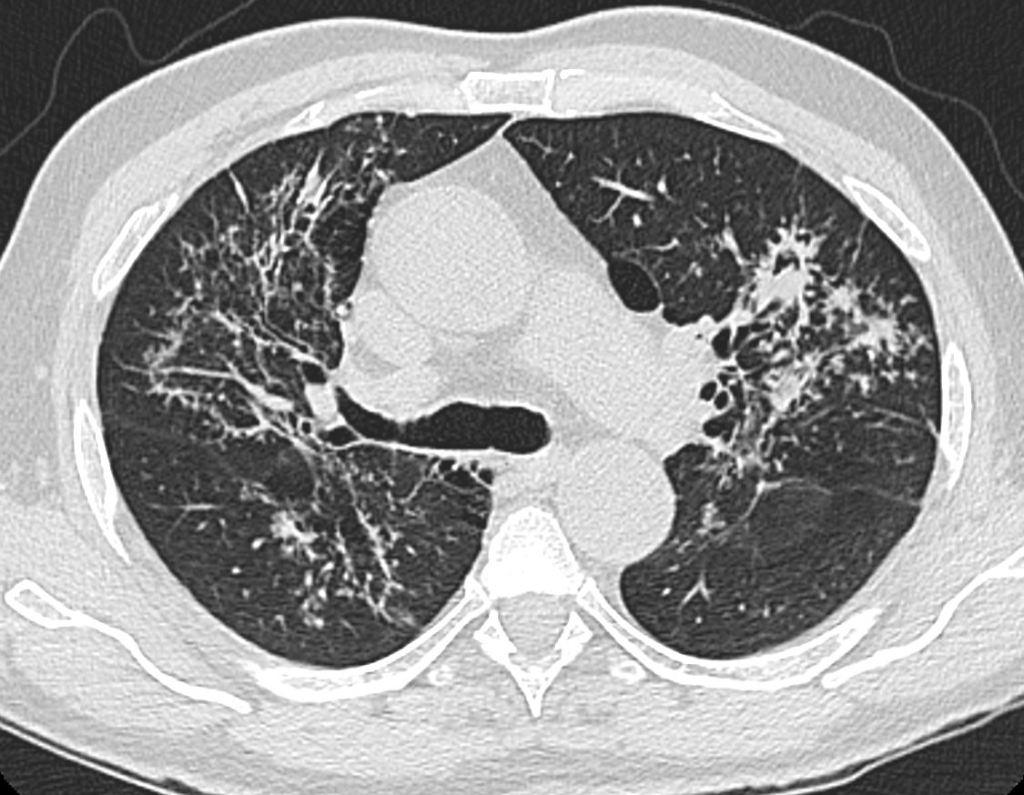

Es un signo visible en la TC correspondiente a una zona de atenuación intermedia -vidrio deslustrado- alrededor de uno o más nódulos pulmonares. Se trata de un signo no específico por lo que puede verse en muchas enfermedades y se debe a la presencia de hemorragia y necrosis perinodular. Está descrito en la aspergilosis, mucormicosis, candidiasis, tumores muy vascularizados (angiosarcoma, sarcoma de Kaposi), metástasis hipervasculares (riñón, corocarcinoma), infecciones virales (citomegalovirus, herpes simplex), tuberculomas y granulomatosis de Wegener.

La imagen corresponde a un paciente con granulomatosis de Wegener.

Este magnífico ejemplo de signo del halo corresponde a un paciente con metástasis de angiosarcoma. Mi agradecimiento a la sección de radiología tórax de mi hospital (Dra. Maribel Padín y Dra. M. Carmen Aguilar) y a Kiko Padilla, que hizo una lectura perfecta del caso.